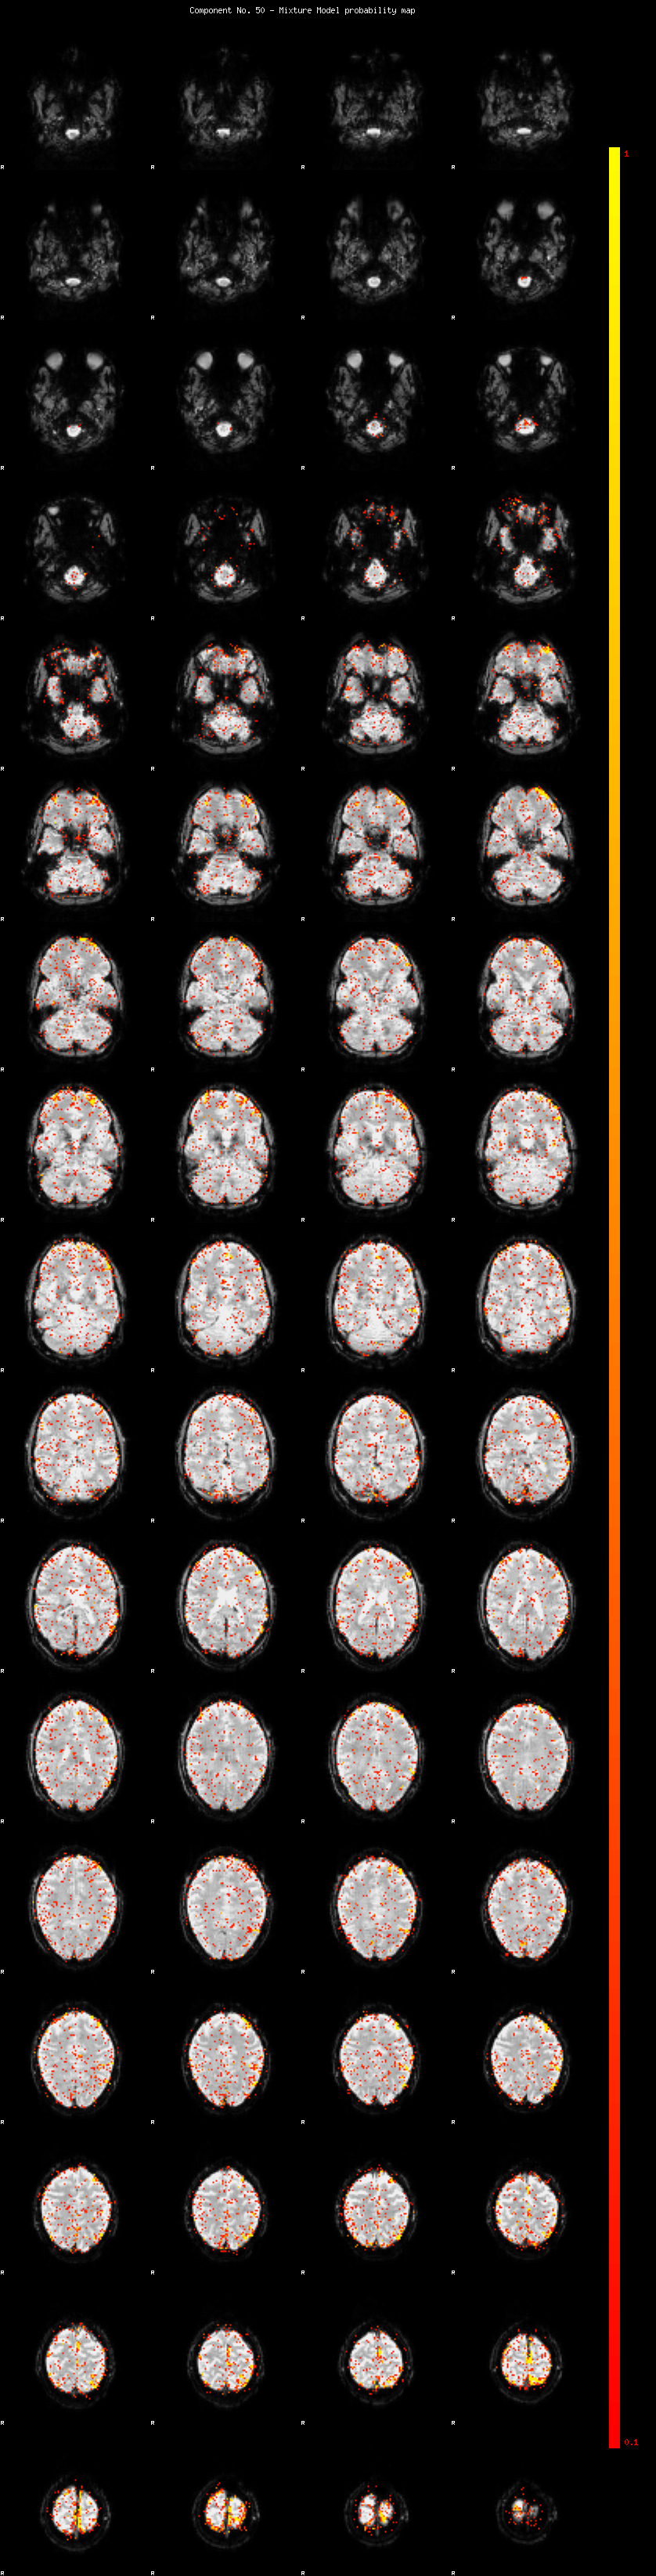

IC_50 Mixture Model fit

Means : -0.000000 2.443673 -2.290607

Vars : 1.000000 1.920419 0.578502

Prop. : 0.961123 0.030653 0.008224